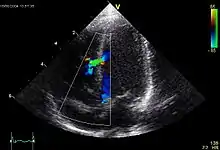

![]() Echokardiogramm eines ASD II, d.h. Ostium-secundum-Typ. |

Atrial septal defect (ASD)

ASD II:

Das heruntergewachsene Septum primum reisst normalerweise in der Mitte ein und bildet das Foramen secundum bzw. Foramen ovale. Dieses wird durch das links vom Septum primum ebenfalls von oben herunterwachsende Septum secundum gardinenartig bedeckt (Ventil) und kurz nach der Geburt durch Umkehr der Druckverhältnisse funktionell (z.T. strukturell durch Verklebung) verschlossen. Ist der Verschluss so ungenügend, dass es zum Links-rechts-Shunt kommt, spricht man vom offenen Foramen ovale bzw. ASD II. Der ASD II ist im Ggs. zum ASD I weiter oben lokalisiert. Er macht oft wenig Symptome und wird oft erst im Erwachsenenalter erkannt. Der Links-Rechts-Shunt kann im EKG zu Zeichen der Rechtsherzbelastung führen (Rechtslagetyp, P pulmonale, inkompletter Rechtsschenkelblock ohne Hypertrophie-Zeichen (rsr's') als Zeichen der rechtsventrikulären Volumenbelastung) und bei starker Ausprägung zu klinischen Symptomen führen.

![]() Echokardiogramm eines VSD. |